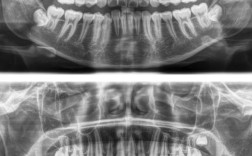

| 全景片(曲面断层片) | 二维影像,显示全口牙齿、牙槽骨、颌骨及部分颌面部结构 | 观察牙齿排列、牙胚发育、牙根形态、牙槽骨高度,发现多生牙、埋伏牙、囊肿等问题 |

(图片来源网络,侵删)- 全景片/根尖片:患者站立或坐姿,下巴置于托架上,额头贴紧固定架,咬住咬合板,保持10-15秒不动。